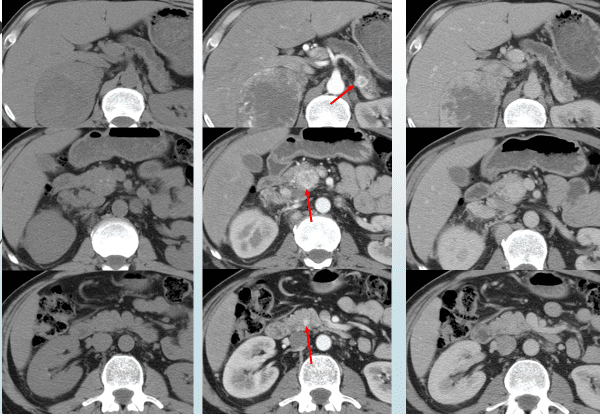

Рисунок 1. Множественные нейроэндокринные опухоли поджелудочной железы. Определяются только на фоне внутривенного введения контрастного препарата.